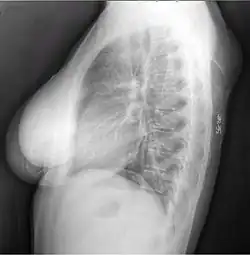

X-ray showing lipoma -